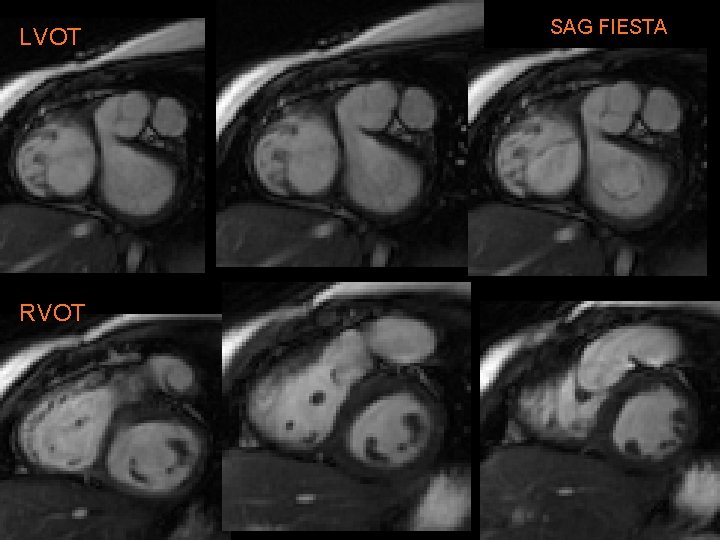

LVOT RVOT SAG FIESTA

A. R. • Treated with modified Norwood & Rastelli procedure: § Conduit from RV to pulmonary artery (w/AV) § Large baffle across VSD from LV to “neoaorta” • Constructed from Ao arch, descending Ao, MPA. • Ao root is anastomosed to neoaorta. • “Systemic valve” is PV § Closure of ASD § Repair of coarct.